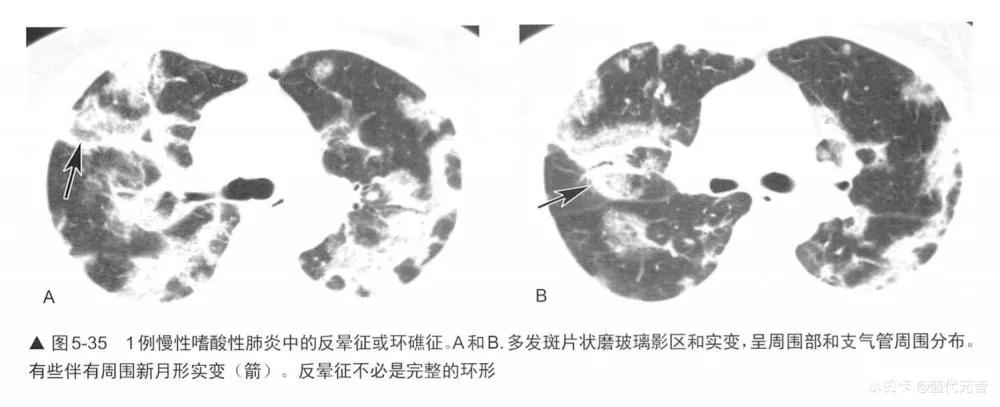

■实变和“反晕征”或“环礁征”

局灶区实变或磨玻璃影可出现所谓的“反晕征”或“环礁征”,这时磨玻璃影被致密的环或新月形实变包绕(与珊瑚环礁相似,或“晕征”的反义词)(图4-47,图5-34,图5-35)。 这种表现高度提示0P,在两篇不同的研究中其发生率为12%和19%。它也常见于慢性嗜酸性肺炎,后者非常像0P。反晕征或环礁征也见于其他疾病的报道,如Wegener肉芽肿(多血管炎性肉芽肿);各种感染,尤其是副球孢子菌病,毛霉菌病,曲霉菌病,细菌性感染和结核;结节病; 肿瘤;淋巴瘤样肉芽肿病和梗死。值得注意的是,这些疾病都可能合并组织学上的0P。在几篇这种少见表现的报道中,磨玻璃影主要符合肺泡间隔炎症,而致密的实变区代表肺泡内炎性浸润。

虽然该征提示0P,但也可见于多种感染性和非感染性疾病。因此,该征象的存在并不能直接排除其他可能的诊断。深入分析HRCT的其他征象有助于鉴别诊断,为了最终确定原因常需组织学评估。

在最近的一项研究中,比较了结核和隐源性机化性肺炎(COP)中反晕征的形态学特点。全部12例活动性结核HRCT上有结节样壁的反晕征,大多数病例(10/12)晕内还可见结节。10例COP未见结节样壁的晕或伴有结节。